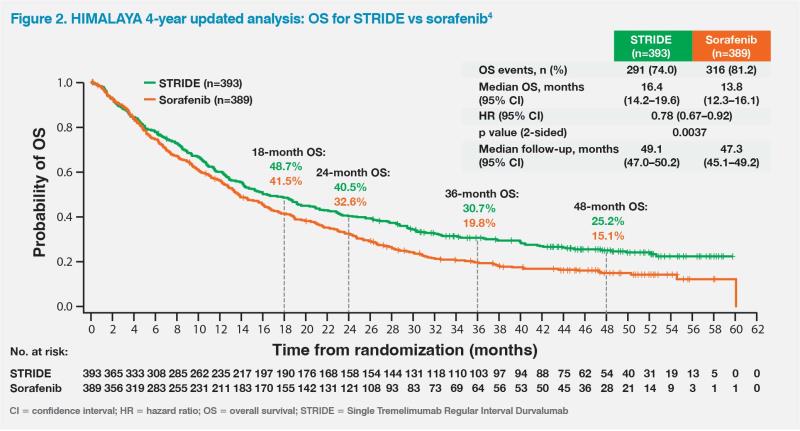

The patient’s ongoing 5-year survival while on the STRIDE regimen is consistent with results of the randomized, multicentre, phase III HIMALAYA trial, which compared STRIDE (n=393) with durvalumab monotherapy (n=389) and sorafenib (n=389) in patients with unresectable HCC and no previous systemic treatment.3,4 After a median follow-up of approximately 33 months, STRIDE significantly improved OS vs sorafenib (median, 16.4 vs 13.8 months; hazard ratio [HR], 0.78; 96.02 percent confidence interval [CI], 0.65–0.93; p=0.0035), while durvalumab monotherapy was noninferior to sorafenib for OS.3

Remarkably, 25.2 percent of patients in the STRIDE arm were still alive at 4 years vs 15.1 percent with sorafenib, which was highlighted by the study’s authors as an unprecedented survival rate in this disease setting.4 (Figure 2)

While the Kaplan–Meier estimates for median progression-free survival were similar for STRIDE and sorafenib, 12.5 percent of patients receiving STRIDE remained progression-free at the final data cutoff vs 4.9 percent with sorafenib.3 In addition, 46.9 percent of patients in the STRIDE arm continued to receive treatment for at least one cycle after objective disease progression, which is reflective of the strategy employed in this case, as the patient continued to benefit from treatment even after developing a new bone metastasis and liver recurrence, suggesting that progression may not necessarily imply resistance to immunotherapy.3

The HIMALAYA trial also showed that complete and partial responses (PR) are considerably more likely in patients with unresectable HCC treated with immunotherapy vs the previous standard of care, sorafenib. The objective response rate (ORR) among long-term survivors (≥36 months beyond randomization) was 51.5 percent with STRIDE vs 53.2 percent with durvalumab vs 15.6 percent with sorafenib. In the STRIDE and durvalumab arms, complete response (CR) rates were 11.7 and 6.3 percent, respectively, while no patients achieved a CR with sorafenib. Respective PR rates were 39.8, 46.8, and 15.6 percent.4

While on STRIDE, the patient developed mild pruritus and hypothyroidism, which were easily managed. In the HIMALAYA trial, these adverse events (AEs) occurred in 22.9 and 12.1 percent of patients receiving STRIDE, respectively.3 Other common any-grade AEs were diarrhoea (STRIDE: 26.5 percent, durvalumab: 14.9 percent, sorafenib: 44.7 percent), rash (22.4, 10.3, and 13.6 percent, respectively), decreased appetite (17.0, 13.7, and 17.9 percent, respectively), and fatigue (17.0, 9.8, and 19.0 percent, respectively). The updated HIMALAYA analysis did not identify new safety signals, indicating that long-term survival achieved with STRIDE or durvalumab was not associated with any substantial safety issues.4